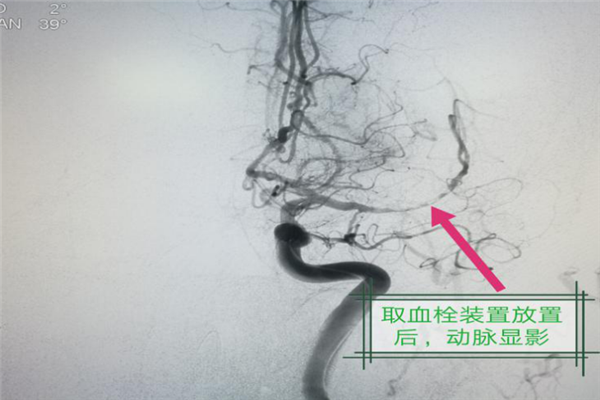

“快!通知介入室,馬上進(jìn)行手術(shù)”,同時(shí),林濤主任安排田瑞瑞護(hù)士長(zhǎng)迅速進(jìn)行圍術(shù)期的相關(guān)治療準(zhǔn)備。手術(shù)臺(tái)上,林濤主任聚精會(huì)神,馮磊、張洋以及介入科醫(yī)生配合默契,爭(zhēng)分奪秒,穿刺股動(dòng)脈,建立動(dòng)脈血管鞘通路,腦血管造影證實(shí)患者確為左側(cè)大腦中動(dòng)脈起始部急性閉塞,病情危重且手術(shù)風(fēng)險(xiǎn)大,手術(shù)團(tuán)隊(duì)的所有人全力以赴,分秒必爭(zhēng)。半個(gè)小時(shí)后,當(dāng)支架取栓系統(tǒng)成功取出堵住患者腦血管的血栓,左側(cè)大腦血運(yùn)恢復(fù)正常,大家這才松了一口氣....手術(shù)室外,家屬焦急的等待著,患者的老伴兒也是七旬高齡的老人,她時(shí)不時(shí)的站起來(lái)看著“介入室”的門(mén)牌赫然亮著的紅燈是否熄滅。當(dāng)患者被推出手術(shù)室,林濤主任告訴家屬,術(shù)中患者生命體征穩(wěn)定,手術(shù)過(guò)程非常順利,家屬激動(dòng)的握著林濤主任的手,連忙說(shuō)“謝謝,謝謝......”